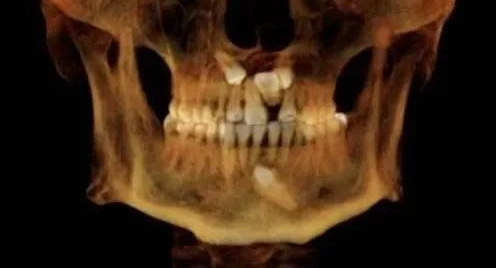

(7)种植牙。CBCT设备可以辅助种植手术的设计,制作种植导板,精确控制种植体的位置、方向、长度、直径等,最大程度利用患者现存骨量,优化种植体的位置,避免在种植手术过程中不慎破坏神经、鼻窦等解剖结构而导致颜面神经麻痹、鼻窦炎等并发症。使种植手术更安全便捷,确保手术及后期修复的成功。

(8)颌面外科。

(9)正畸等。